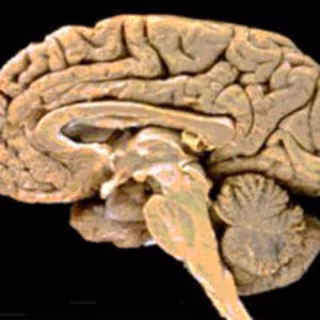

Una región del cerebro llamada la ínsula es parte destacada de la adicción al tabaco y los daños en esta estructura pueden eliminar por completo la necesidad de fumar del organismo, según un estudio de las Universidades de Iowa y California del Sur en Los Ángeles (Estados Unidos) que se publica en la revista 'Science'.

Los resultados de la investigación podrían conducir a terapias para ayudar a los fumadores a dejar el hábito o para controlar el progreso mientras se utilizan las terapias existentes. La ínsula recibe información de otras partes del organismo y se cree que ayuda a traducir esas señales en lo que sentimos de forma subjetiva.